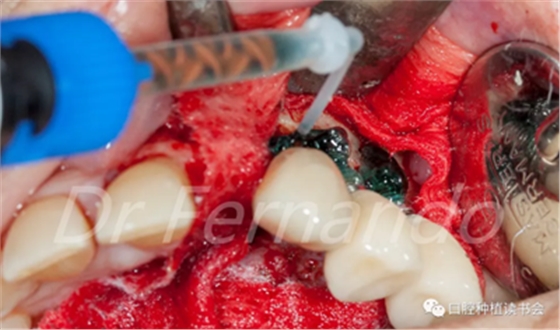

在種植體周圍放置無菌敷料以保護周圍的骨壁和軟組織;用生理鹽水濕潤改善粘附性。用注射器將37%磷酸和2%洗必泰組成的凝膠涂抹在整個種植體表面,讓凝膠作用2分鐘,以促進種植體表面生物膜的分解(圖13 )。

圖13 使用磷酸與洗必泰混合凝膠去除生物膜

處理2分鐘后,用無菌的吸唾管吸除凝膠,用生理鹽水沖洗種植體表面10秒,然后用無菌吸唾管吸除剩余的鹽水溶液,取出敷料。下一步是用無菌敷料包住種植體,用透明質(zhì)酸鈉-哌拉西林-他唑巴坦溶液浸泡5分鐘后取出(圖14)。

圖14 使用抗生素溶液凈化種植體表面